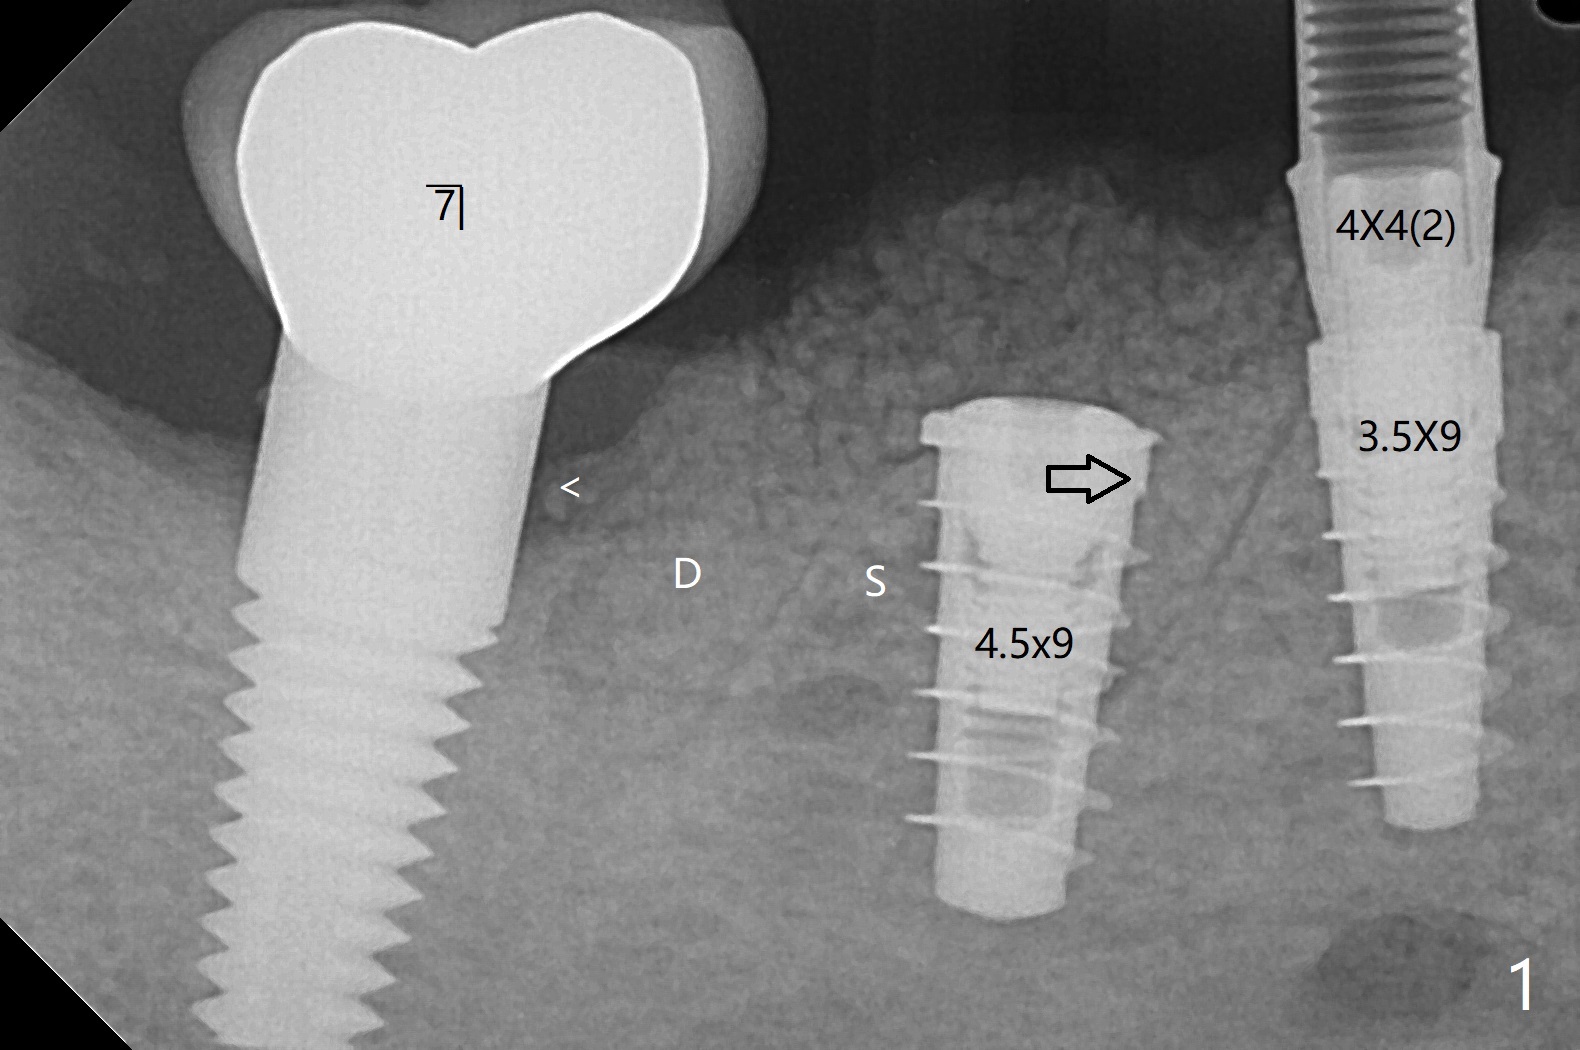

右下5,6植体植入后,取下导板,发现两者都植入不够深,放回导板,5植体植入深点(35Ncm),但是6植体与植牙工具通过导板接不上,正好取出导板,徒手旋紧,不幸的是植体往近中移位(图一:空箭头,远离中隔(S)),稳定性好像降低,不适合即刻修复,放置愈合螺帽后,大量植入粘性骨粉,包括进入7近中(短箭头,事先需要往上分离龈乳头),覆盖PRF膜,PGA缝线,利用5基台,固定树脂敷料。术后5个星期,撤除树脂敷料,虽然愈合螺帽暴露,周围牙龈健康,并含有骨粉(图二)。术后两个月植体基本被覆盖(图三),术后3.5个月植体完全覆盖,切开前根尖片显示植体平台与牙槽嵴平齐(图四),术中证实。5基台好像没有就位(图四(可能拍摄角度不佳)),将基台平面从远中旋转至颊侧,就位仿佛改善(图五)。术后四个月6放置基台后(图六),制作连体5,6牙冠,垫高(打开咬合),近中衬里,推4,关闭3,4之间间隙(图三)。6植体远中第一个螺纹好像暴露。